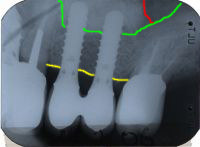

Abb. 3 - Sinuslift mit gleichzeitigem Setzen von drei Implantaten im Oberkiefer rechts. Transplantationsgemisch: 2/3 Eigenknochen und 1/3 Substitut.

Abb. 4 - Sinuslift mit gleichzeitigem Setzen von zwei Implantaten im Oberkiefer links. Transplantationsgemisch: 10% Eigenknochen und 90% Substitute. Das konnte ich mir erlauben, weil viel ortsständiger Eigenknochen vorhanden war.

Verlauf des Kieferhöhlenbodens vor

Sinuslift

Verlauf des Kieferkammes

-Gebiet zwischen gelber und grüner

Linie: ortsständige Knochenhöhe.

neuer Verlauf des Kieferhöhlen-

bodens nach Sinuslift.

-Gebiet zwischen roter und grüner

Linie: Knochenaufbau, Sinuslift.